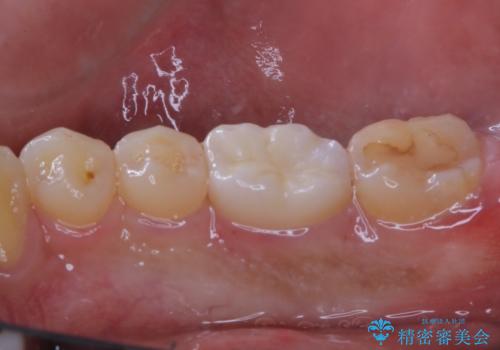

- セラミックへのやり替えを希望された患者様です。

日常的に食いしばる癖があり、歯の表面にはエナメルクラック(歯の表面にできる細かい破折線)も複数認められたため、セラミッククラウンによる治療をご提案しました。